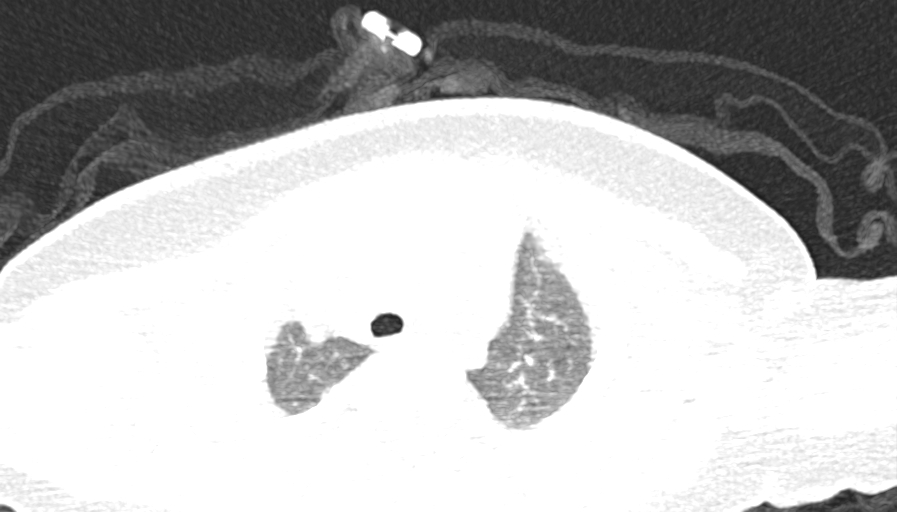

PED5449:一月前打过卡介苗,3个月,男 左腋窝肿物。

一月前打过卡介苗,3个月,男 左腋窝肿物。是淋巴结Tb并坏死?????还是脓肿并淋巴结肿大?????

左侧腋窝淋巴结增大,周围脂肪组织模糊,考虑感染性病变可能大,请结合临床。

左腋窝多发淋巴结增大,见坏死,周围脂肪内有渗出,考虑感染性病变。纵隔内未见明确异常。

左侧腋下可见结节,边缘欠光整,中央密度低,考虑:左侧腋窝淋巴结肿大。必要时建议增强或MRI检查。排除纵隔占位。

冰冻纵膈- 肺内见不规则斑片状 索条状混杂阴影。肺门不大。余无特记。左侧腋窝见多个肿大淋巴结。余无特记。考虑:纵膈淋巴瘤伴左侧腋窝淋巴结。

肿物40hu。低密度15HU